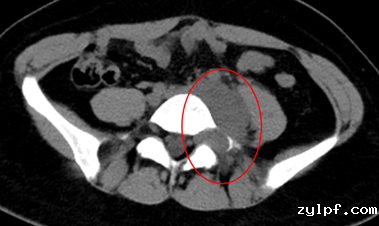

患者21岁女性,因左下腹隐痛2月,检查发现左腰骶椎前占位4天来诊。入院后进一步完善影像学检查提示左侧L5/S1椎间孔及椎体前后方占位。病灶钻缝生长,延伸至椎管内,再沿L5左侧横突孔向后伸至脊柱旁,横突孔增宽增大,骨质变薄,邻近肠管、左侧髂总血管稍推压移位。穿刺活检结果提示神经鞘瘤。

图片 7.png

图片 8.png